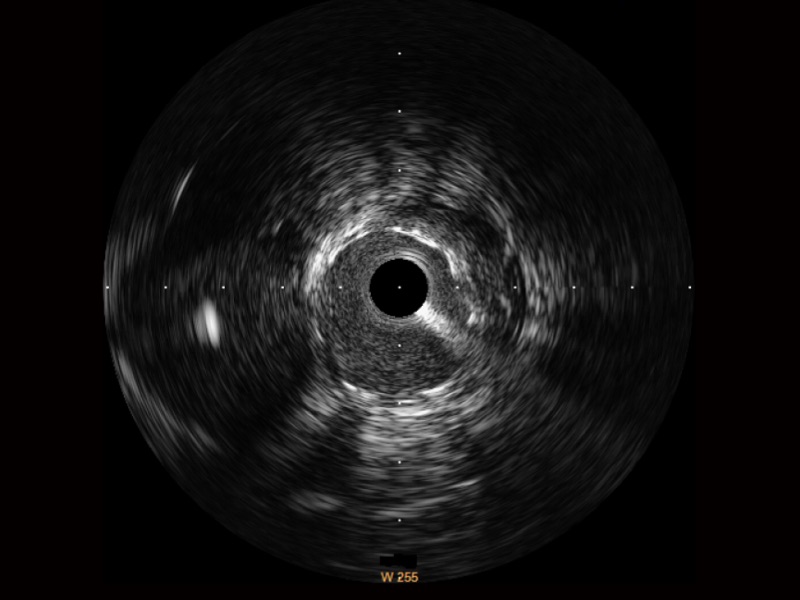

传统IVUS图像

对比传统IVUS导管成像,MILE米乐集团官网宽频IVUS图像的近场支架梁显影更细腻,远场中膜外血管仍清晰可辨,兼顾远中近,兼顾分辨力与穿透深度